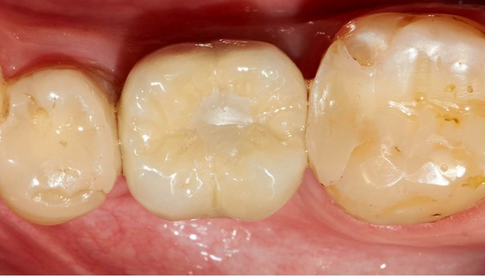

6 months follow-up of #36 implant placementDr. Pavel YaroshevichJul 2, 20151 min readPre-operative Observation- One year after the extraction of #36 Post-operative radiological view.After 10 weeks.6 Months follow-up